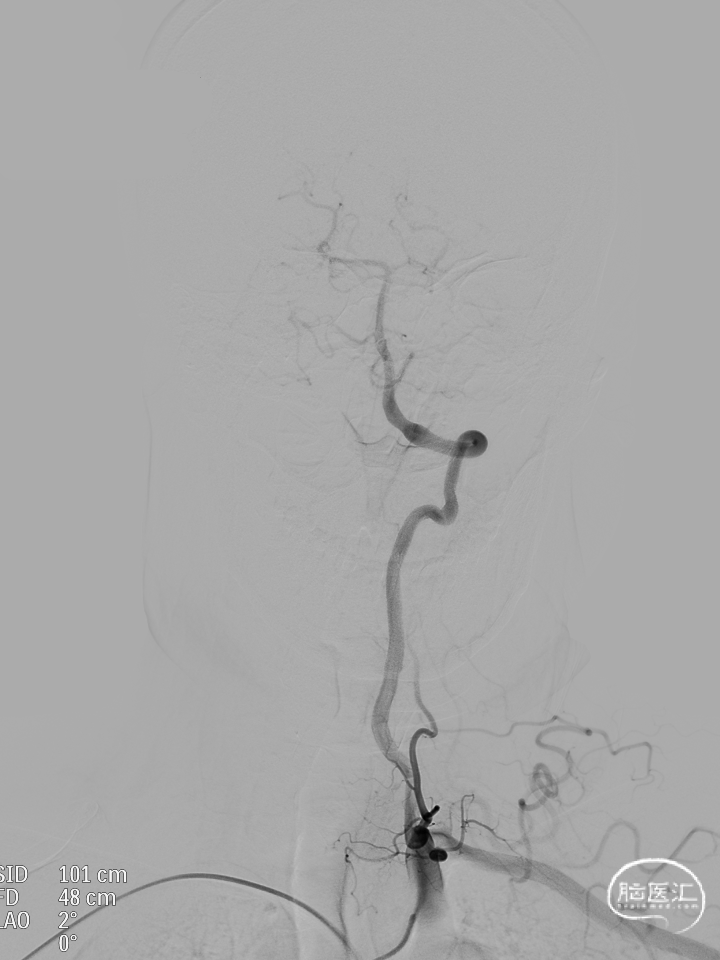

微导管到位:Synchro微导丝引领支架微导管通过病变血管进入大脑中动脉M1段远端。

支架到位,远端打开(正侧位):4.75-20mm支架在大脑中动脉M1段打开,回撤至C6段远端锚定。支架释放过程中,轻柔推送支架系统,可见支架导管沿血管壁大弯侧走行,支架打开良好。

支架中段打开:

输送导丝及微导管回撤:释放至支架末端,减张系统,回撤支架导管,释放支架。沿支架推送杆,调节系统张力,将支架导管通过支架到达C7段。

支架内使用成襻微导丝进行按摩,使支架充分贴壁。

术后造影:支架覆盖两枚动脉瘤瘤颈,贴壁良好,瘤体内可见造影剂滞留。

术后支架显影: